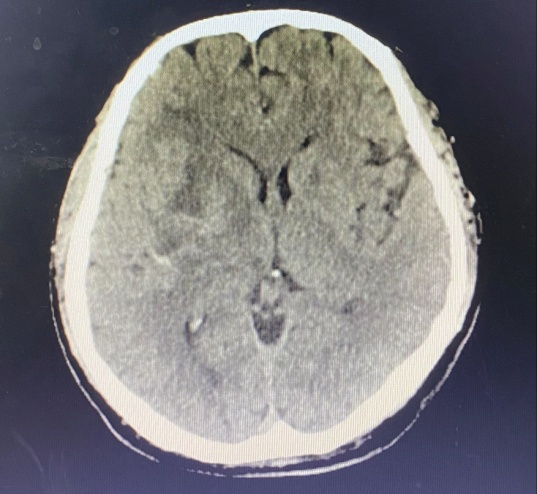

患者黃先生,44歲,4月29日凌晨突感頭痛伴左肢體乏力、言語含糊,被家屬緊急送至我院急診科,立即安排顱腦CT檢查,CT提示為右側(cè)基底節(jié)區(qū)腦出血、丘腦出血,出血量大,約35ml,且中線稍向左偏,周圍腦溝腦回受壓,情況危急。我院神經(jīng)外科立即與聯(lián)盟單位福建醫(yī)科大學(xué)附屬第二醫(yī)院神經(jīng)外科當(dāng)值專家聯(lián)系,考慮到患者尚年輕,決定在CT引導(dǎo)下行右側(cè)基底節(jié)血腫碎吸引流清除術(shù),該手術(shù)具有創(chuàng)傷小、患者恢復(fù)快等優(yōu)點(diǎn),征得家屬知情同意后,立即進(jìn)行手術(shù)治療。

術(shù)前、術(shù)后CT對比

復(fù)查CT提示,患者顱內(nèi)血腫大部分已清除,生命征平穩(wěn)。手術(shù)很成功,但醫(yī)護(hù)人員仍然沒有放松下來。?針對患者的病情,手術(shù)僅僅是個(gè)開始,術(shù)后的恢復(fù)治療同樣關(guān)鍵。福醫(yī)大附二院專家對術(shù)后治療進(jìn)行精心指導(dǎo),我院神經(jīng)外科醫(yī)護(hù)人員也密切監(jiān)測患者生命體征。為了進(jìn)一步促進(jìn)康復(fù),我院康復(fù)理療師對患者進(jìn)行床邊針灸治療,并指導(dǎo)家屬幫助患者進(jìn)行床邊肢體康復(fù)運(yùn)動(dòng)訓(xùn)練。在醫(yī)護(hù)人員精心治療和悉心護(hù)理下,黃先生病情好轉(zhuǎn),穩(wěn)定后予轉(zhuǎn)當(dāng)?shù)蒯t(yī)院進(jìn)一步康復(fù)治療。